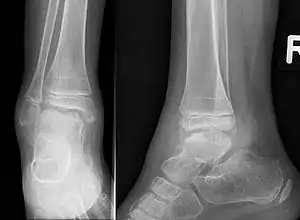

| Trevor disease in a nine-year-old girl: talus | |

Trevor disease, also known as dysplasia epiphysealis hemimelica and Trevor's disease, is a congenital bone developmental disorder. There is 1 case per million population. The condition is three times more common in males than in females.

This disorder is rare, and is characterised by an asymmetrical limb deformity due to localized overgrowth of cartilage, histologically resembling osteochondroma. It is believed to affect the limb bud in early fetal life. The condition occurs mostly in the ankle or knee region and it is always confined to a single limb. This usually involves only the lower extremities and on medial side of the epiphysis. It is named after researcher David Trevor.[1]

Trevor disease was first described by the French surgeon Albert Mouchet and J. Belot in 1926. In 1956, the name "dysplasia epiphysealis hemimelica" was proposed by Fairbank.[1] The usual symptoms are the appearance of an osseous protuberance, on one side of the knee, ankle or foot joint which gradually increases Radiologically,[14] the condition shows a nonuniformity of growth and multiple unconnected ossification centers around the epiphyses.[8]